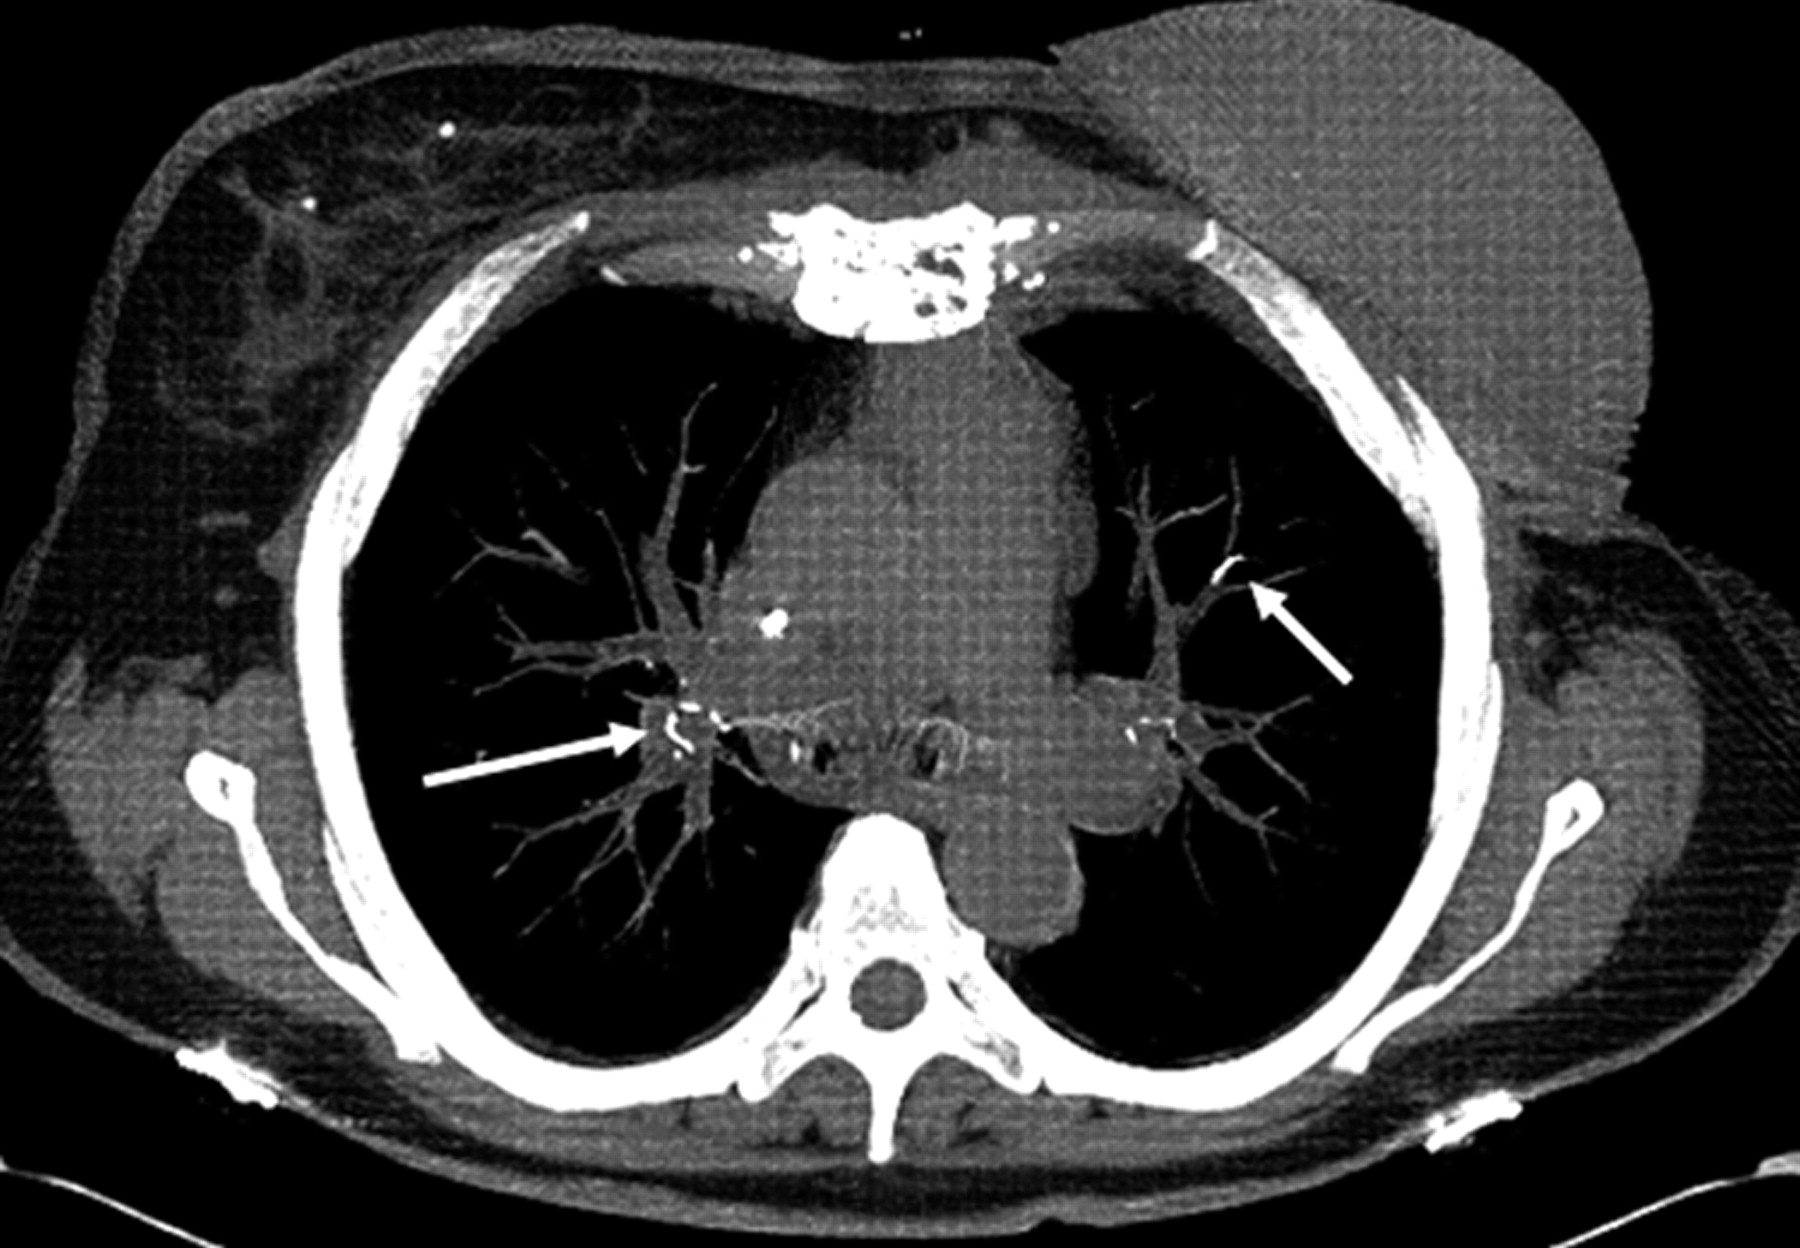

A 68-year-old woman treated with vertebroplasty at T12. Axial unenhanced chest CT scan obtained 4 months following vertebroplasty demonstrates linear areas of markedly increased attenuation (arrows) within the pulmonary vasculature, indicating cement PEs.

Among these 23 patients with cement PEs, the mean number of discrete emboli per patient was 3.2 ± 3.4 (median, 2; range, 1–12). Nine (39%) of 23 patients had a single embolus, 6 (26%) had 2, three (13%) had 3 emboli, and 5 (22%) patients had 4–12 emboli. Most emboli were tubular or branching (Figs 1 and 2). The mean length of emboli was 5.0 ± 4.4 mm (median, 4.0 mm; range, 1–21 mm). Cement PEs were scattered throughout both upper and lower lobes of both lungs.